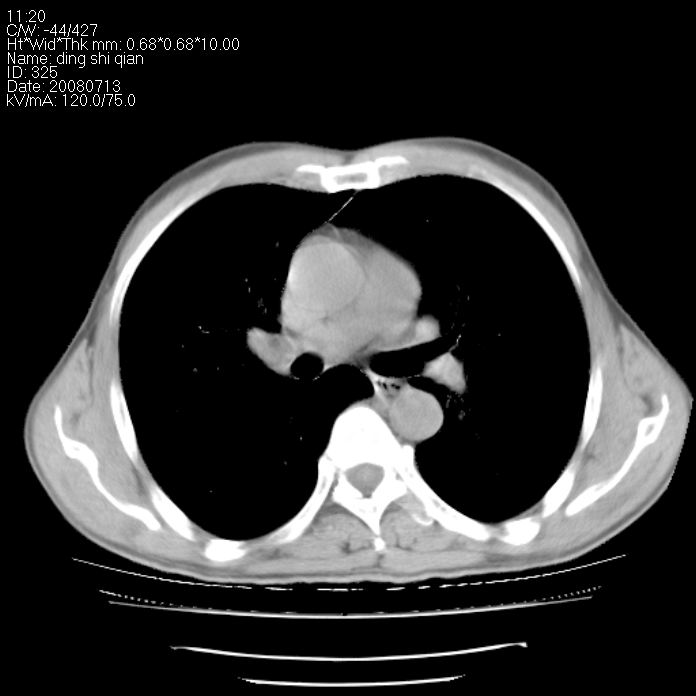

标题: CT14654:男 50岁 近来胸痛 [打印本页]

标题: CT14654:男 50岁 近来胸痛

右侧上肺块状软组织影,浅分叶,边缘毛刺证,与胸膜粘连,考虑:周围性肺癌

右侧上肺块状软组织影,浅分叶,边缘毛刺证,与胸膜粘连,考虑:周围性肺癌!支持!